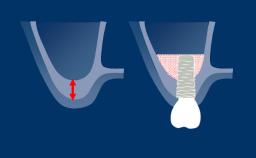

When people have lost teeth, they meet the definition of the World Health Organization - WHO - of being "physically impaired", because they have lost a body part.

All patients who are missing teeth have an impairment. Some also meet the WHO definition of being "disabled", because they have lost at least some of their ability to chew, particularly foods that are tough or hard.

As with those who have lost a limb, we cannot replace these body parts; we can, however, provide prostheses that are designed to replace lost function and esthetics. In today's world, the patient is a consumer of health care services. Thus, satisfaction with the care they receive, as well as the decision-making process, is not only in the hands of the clinician.